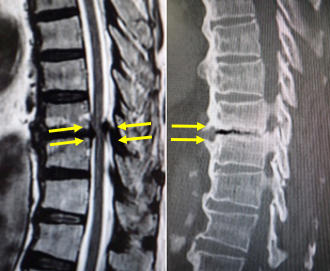

腰(左)胸椎に肺癌の転移性腫瘍を認めます。脳転移などもあったため、根治的手術は困難でした。(中、右)経皮的椎弓根スクリューを用いた特殊な方法で、脊椎を安定化しています。 術後、麻痺の改善と疼痛の緩和を認めました。 -

腰の第4番目、5 番目の椎体が感染し、進行性の骨破壊と後弯変形を認めます。経皮的椎弓根スクリューを用いた特殊な方法で、脊椎を安定化しています。 -

(左)術前の進行性の骨破壊が見られましたが、(右)術後1年では良好な骨癒合が得られています。